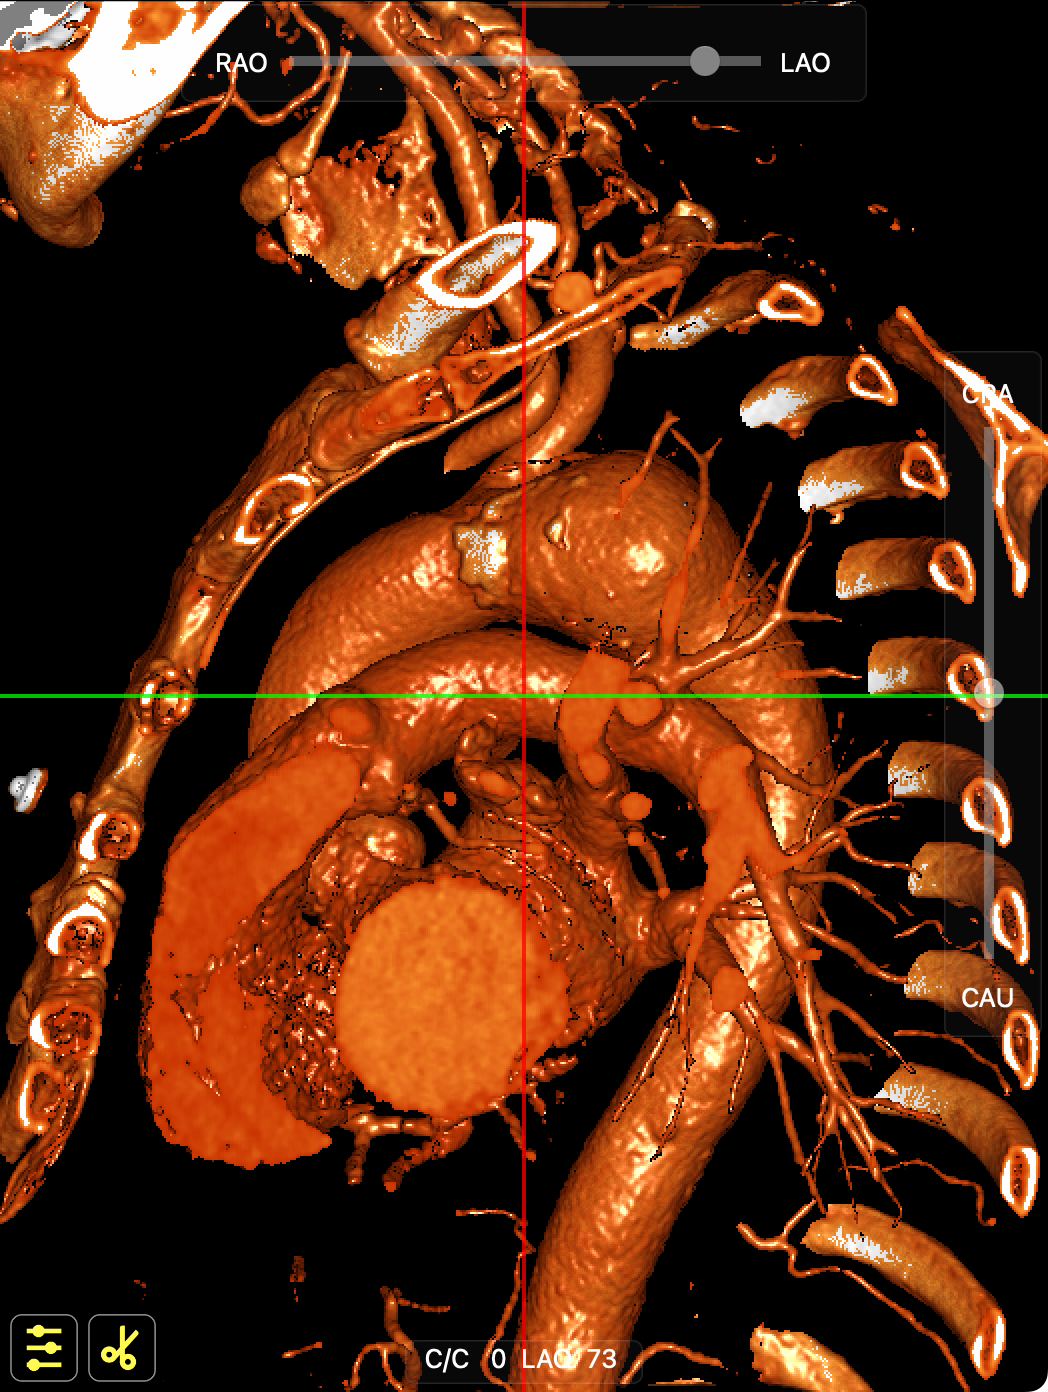

CT影像

CT影像